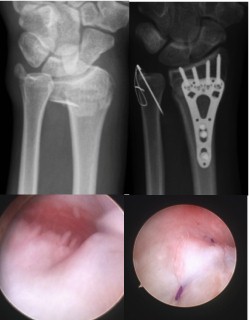

Sports and Traumatic Injuries of the Wrist

Our expertise extends to the treatment of a substantial number of traumatic and sports-related injuries affecting the wrist, including overuse syndromes. Common bone injuries involve fractures of the distal radius and scaphoid, while ligament injuries of the wrist include tears of the scapholunate ligaments and triangular fibrocartilage complex. Although dislocations involving the main articulations of the wrist joint and intercarpal dislocations are less common, our team is well-equipped to manage such issues.

Treatment modalities vary based on the severity of the injury or condition, ranging from splinting and occupational therapy to casting or, when necessary, open and minimally invasive surgical interventions. Wrist arthroscopy is used as both a diagnostic tool and for therapeutic management in select ligament injuries of the wrist. For cases of chronic ligament instability of the wrist typically characterised by pain, functional limitations and recurrent dislocations, ligament reconstruction surgery reliably alleviates pain and restores function.

Open reduction and internal fixation of a distal radius and ulnar styloid fracture (top) Arthroscopic repair of TFCC injury (bottom).